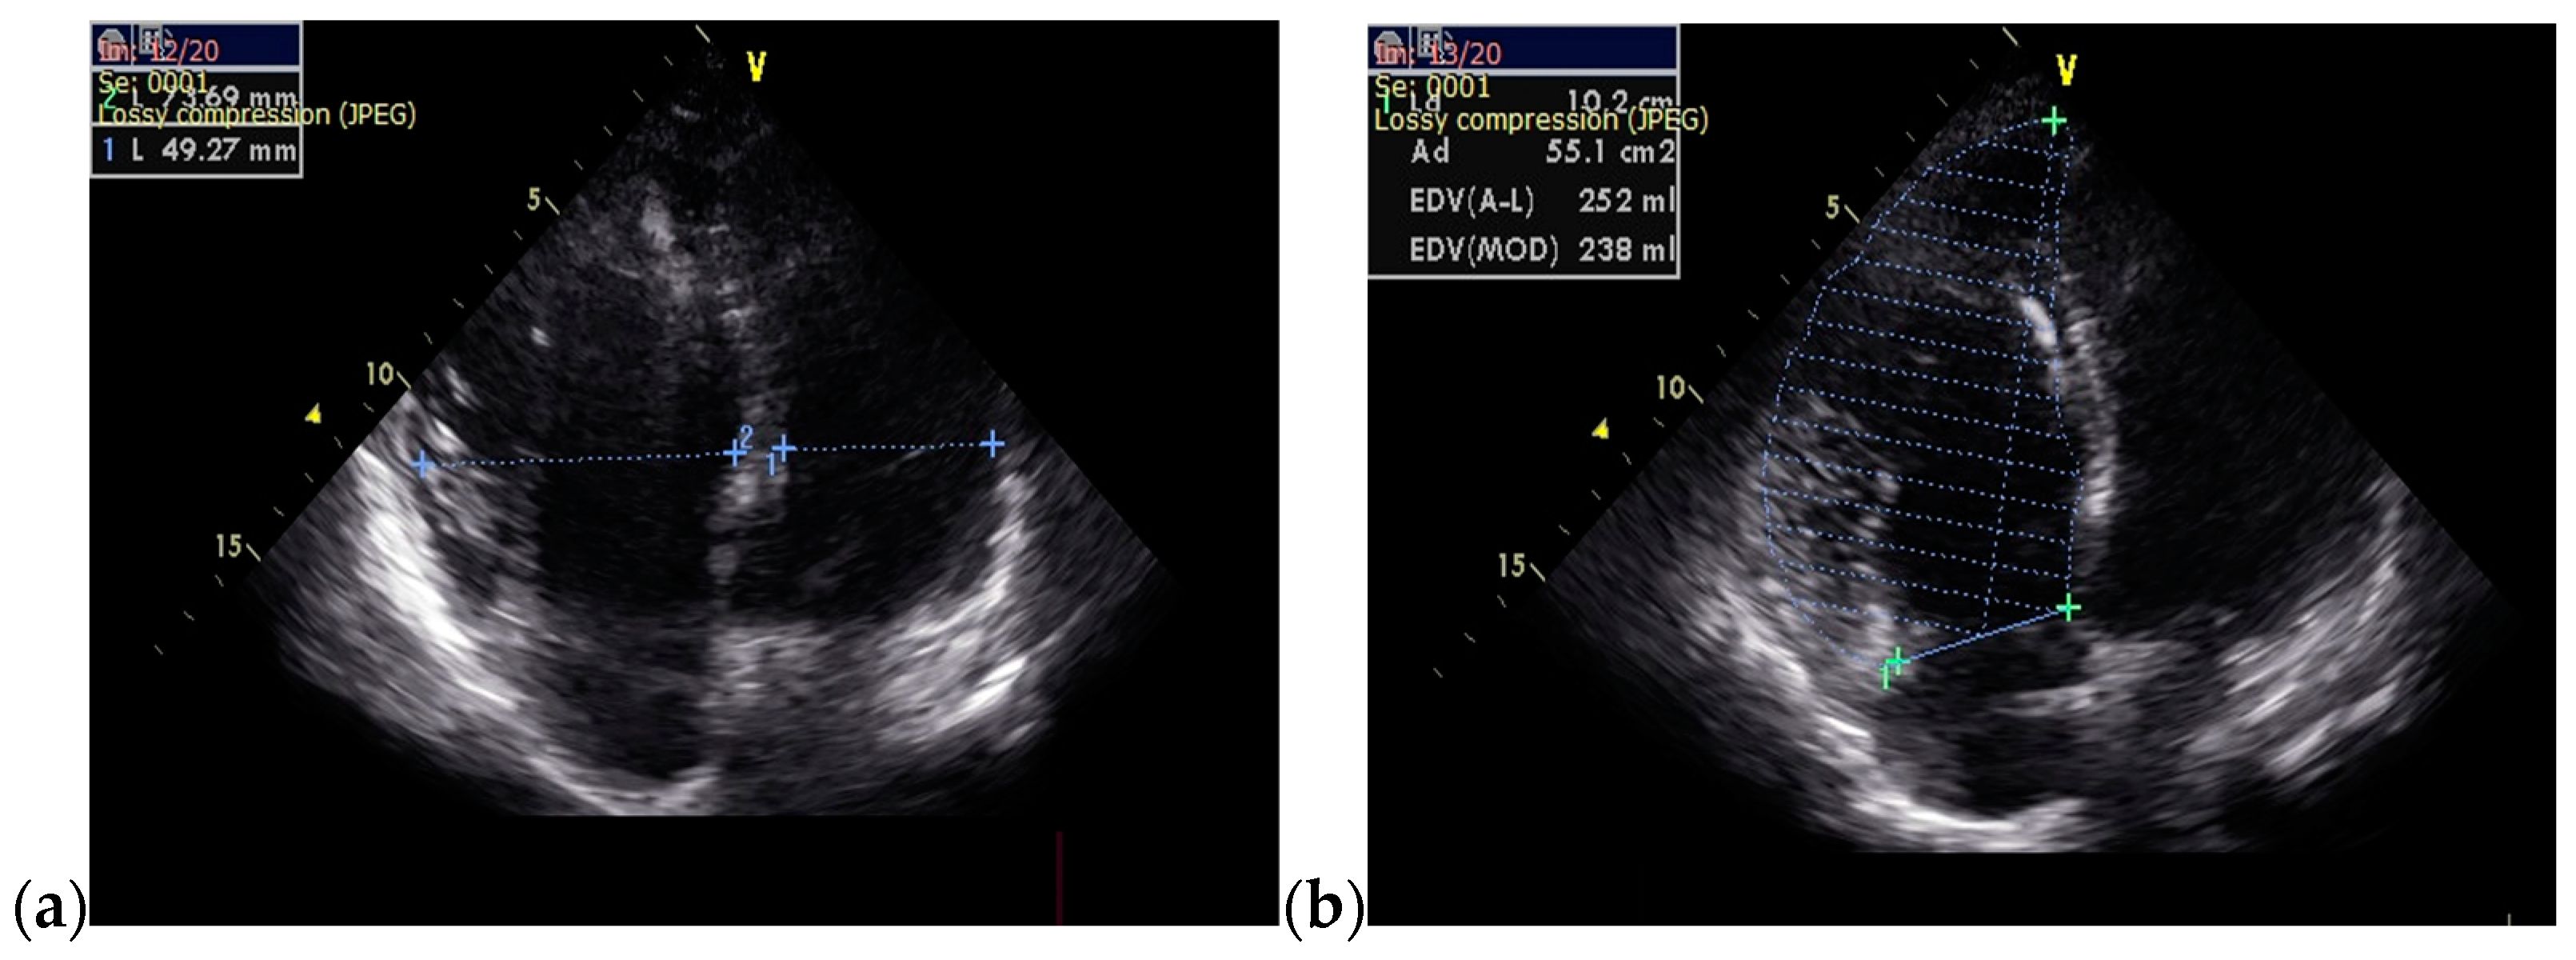

The follow-up TTE evaluation demonstrated a nondilated left ventricle with preserved ejection fraction, dilated right chambers, an increased total volume of RV measuring 339 mL and atrialized RV with a volume of 135 mL, severe functional tricuspid regurgitation, insertion of the septal cusp of the tricuspid valve approximately 2.9 cm from the plane of the tricuspid annulus and ventricular pacing electrode (Figure 12).

Figure 12.

The TTE follow-up evaluation: (a) Apical 4-chamber view: dilated right cavities with a total volume of RV measuring 339 mL; (b) Apical 4-chamber view: atrialized RV volume of 135 mL; (c) Apical 4-chamber view: color Doppler flow revealing severe tricuspid regurgitation; (d) Tricuspid continuous wave Doppler flow: maximum RV-RA gradient = 33.45 mmHg; (e) Apical 4-chamber view: insertion of the septal cusp of the tricuspid valve at approximately 2.9 cm from the plane of the tricuspid annulus; (f) Apical 4-chamber view: end-diastolic left ventricular volume—110 mL. Abbreviations: TTE—transthoracic echocardiography; RV—right ventricle, RA—right atrium.